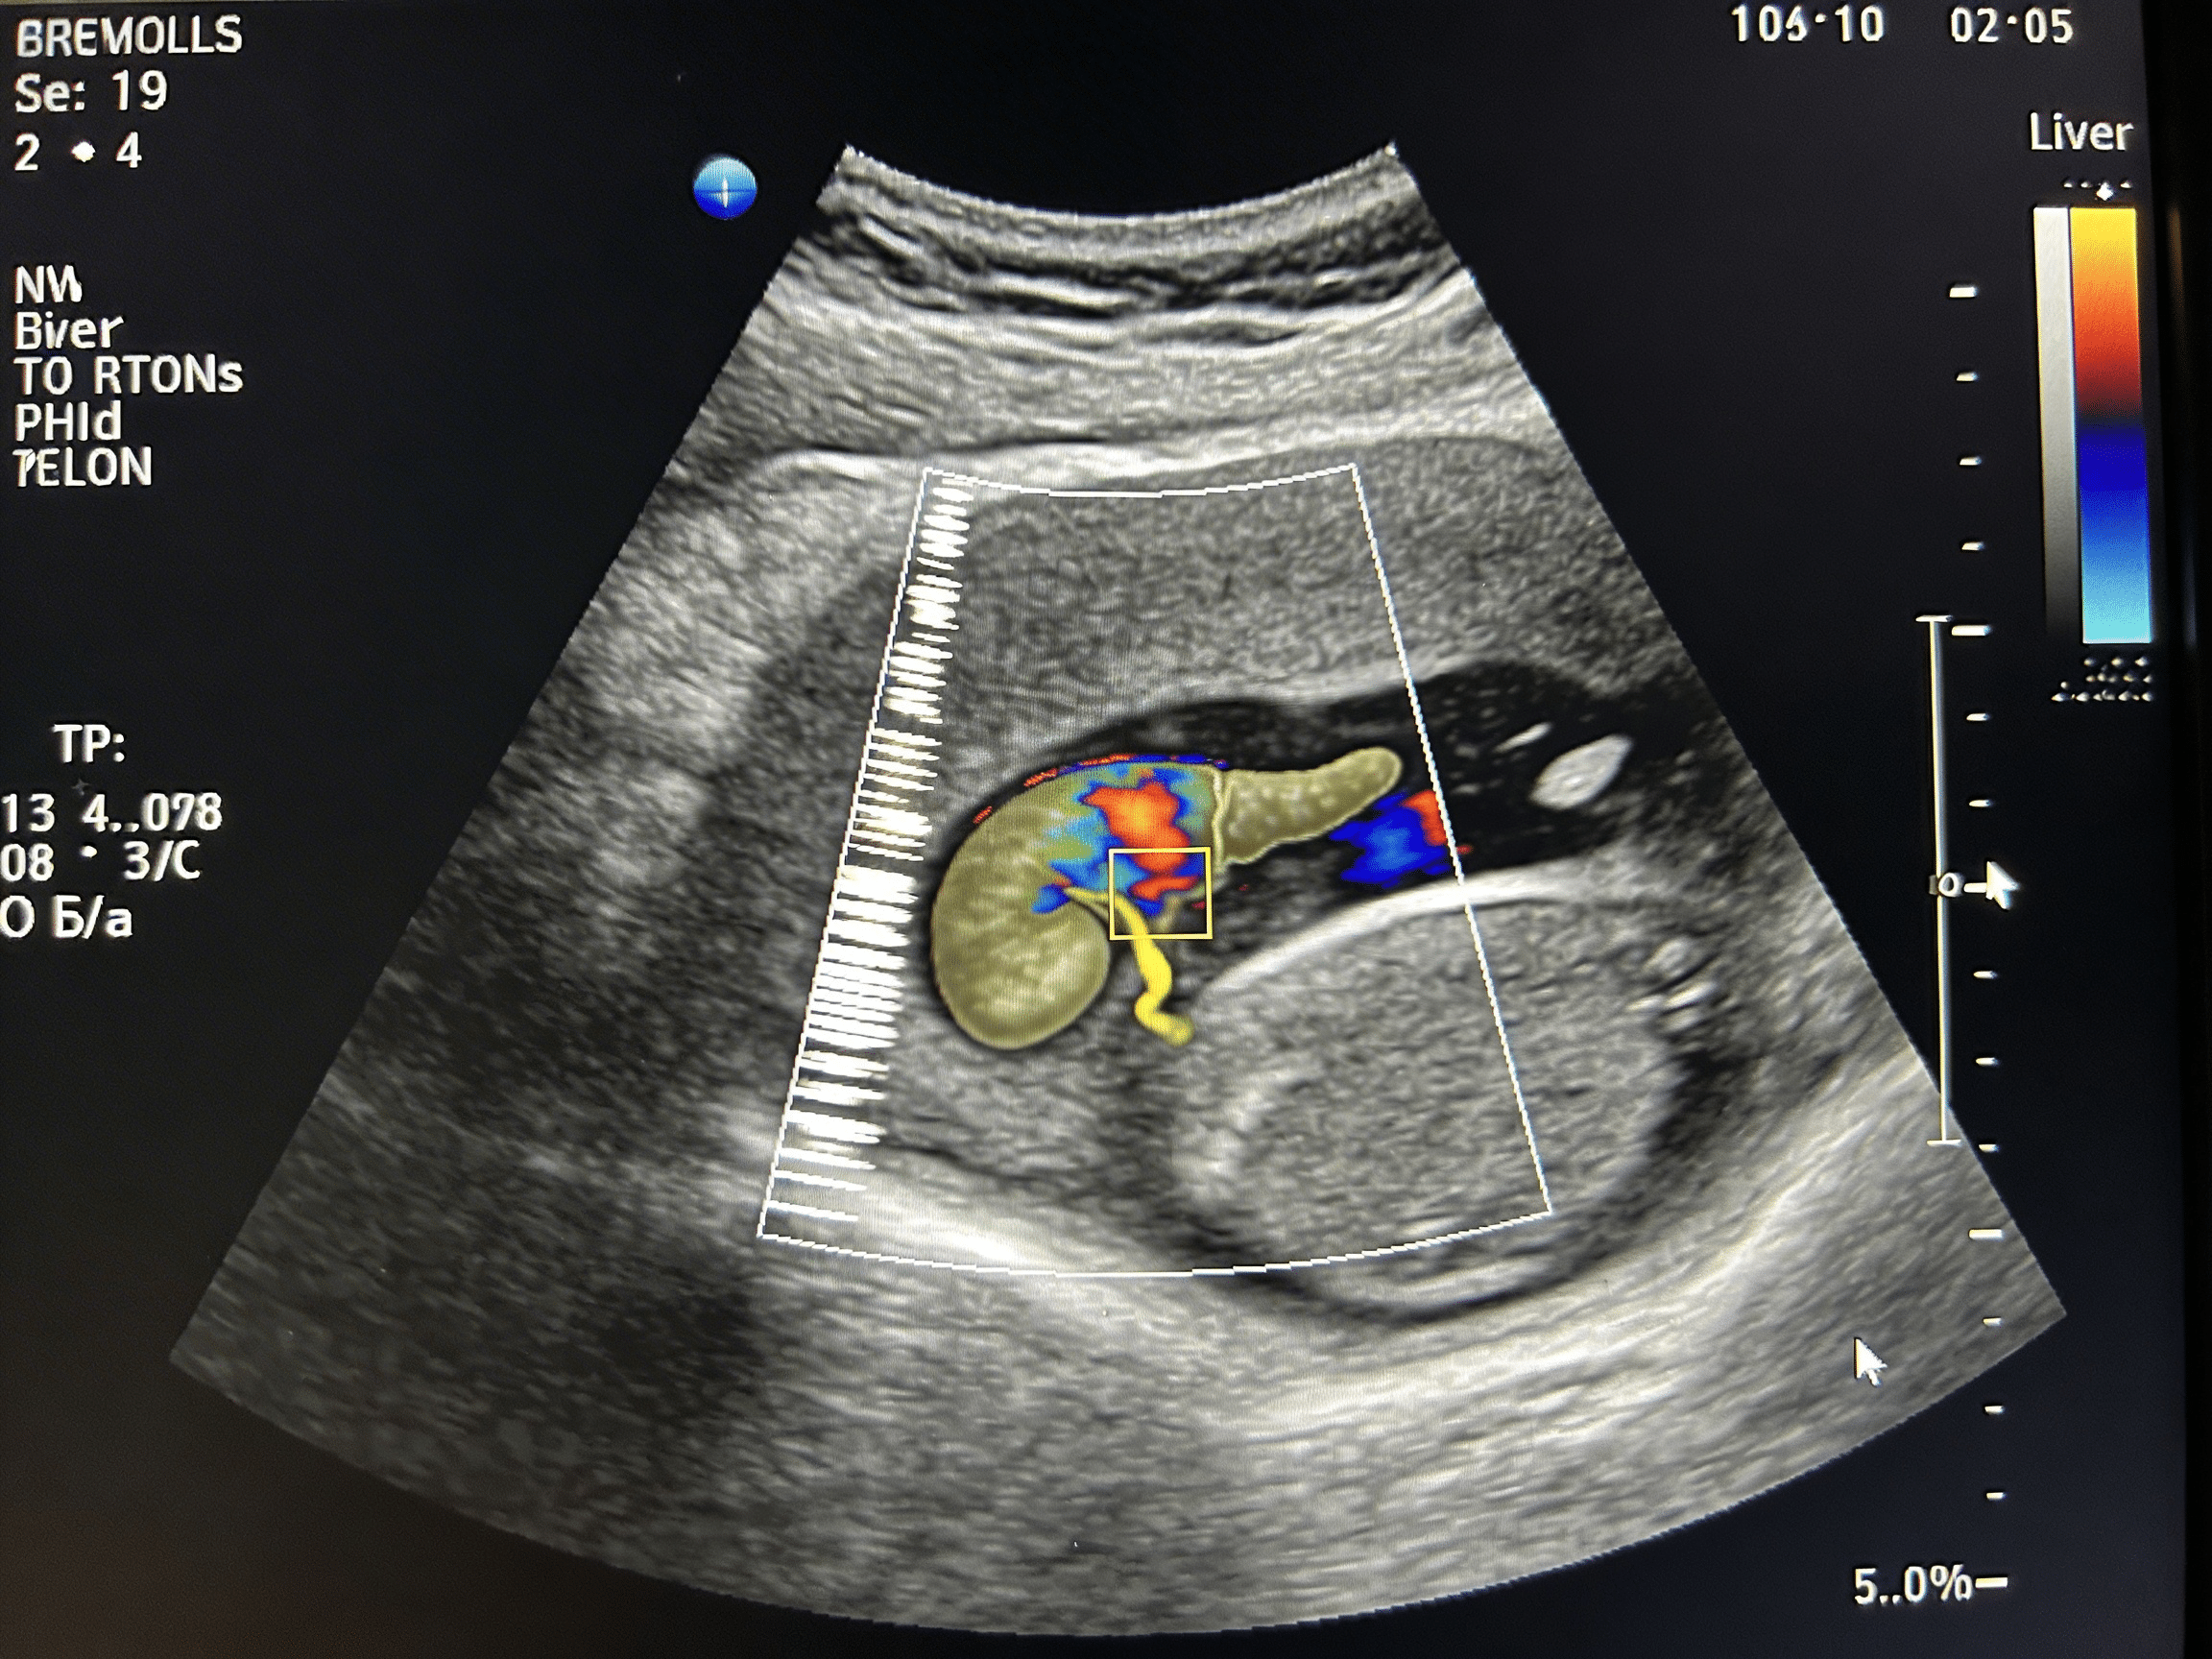

Priority ER's diagnostic capabilities for ultrasound (FAST) for internal fluid, DVT evaluation, or gallbladder inflammation exceed Joint Commission standards for emergency departments[14], featuring high-resolution portable ultrasound machines enabling immediate bedside assessment without transporting unstable patients to radiology departments. Our emergency physicians trained in emergency ultrasound perform FAST exams with 86-97% sensitivity for detecting hemoperitoneum in hypotensive patients, compression ultrasound with 95% sensitivity for proximal DVT detection, and right upper quadrant ultrasound identifying gallstones, gallbladder wall thickening, and Murphy's sign confirming acute cholecystitis with 88% sensitivity[15]. The integration of color Doppler imaging identifies absence of venous flow confirming DVT diagnosis, spectral Doppler assesses respiratory variation distinguishing acute versus chronic thrombosis, and power Doppler detects gallbladder wall hyperemia indicating acute inflammation requiring urgent surgical intervention.

Advanced imaging through our comprehensive diagnostic capabilities provides extended FAST (E-FAST) adding bilateral thoracic views detecting pneumothorax with higher sensitivity than chest x-ray, evaluation for IVC collapsibility assessing volume status guiding resuscitation, and cardiac ultrasound identifying pericardial effusion with tamponade physiology requiring emergency pericardiocentesis. For DVT evaluation, our emergency physicians perform complete lower extremity venous mapping from common femoral vein through posterior tibial and peroneal veins when clinical suspicion remains high despite negative compression ultrasound in proximal veins. This comprehensive approach explains why the American College of Emergency Physicians supports emergency physician-performed point-of-care ultrasound as standard practice, improving diagnostic accuracy from 75% (clinical examination alone) to 96% (examination plus bedside ultrasound).